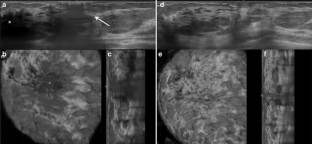

Fig. 1